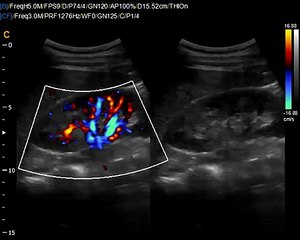

Q5 by Chison imaging Fetal Heart sonogram, easy to see heart in fetus, neonatal ultrasound